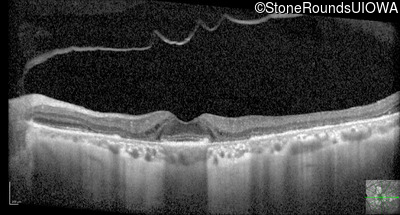

Optical Coherence Tomography - Right - 20/25 -2

Exemplar / OCT Stack

OCT Stack